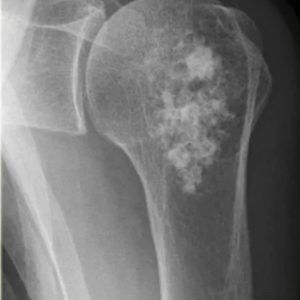

В основе инновационной разработки — радионуклид радий-223. Препарат «Ракурс, 223Ra» предназначен для лечения определённых видов онкологических заболеваний, преимущественно при метастазах в костях.

Радиоактивное излучение 223Ra целенаправленно воздействует на костные метастазы, уменьшая болевой синдром и улучшая качество жизни пациентов.